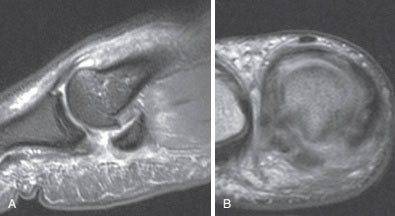

Мы в качестве наиболее информативного метода визуализации связочных и остеохондральных повреждений рассматриваем МРТ.

МРТ позволяют достаточно четко увидеть все типы повреждений и более точно локализовать возможные разрывы связок и капсулы и спланировать хирургическое вмешательство.

МРТ при тяжелом повреждении связок первого пальца. А, На МРТ видны признаки разрыва связок и смещение сесамовидной кости. В, На МРТ видны признаки полного разрыва медиальной коллатеральной связки при сохранении целостности аналогичной латеральной связки.